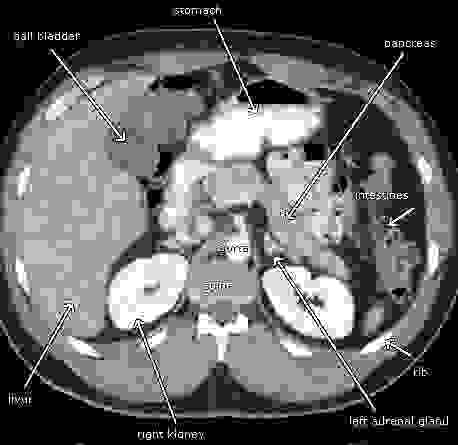

Section image

Tomografía Computada Abdominal

Para evaluar los órganos internos, incluídos el hígado,

riñones, páncreas y tracto gastrointestinal.

Saber mas...